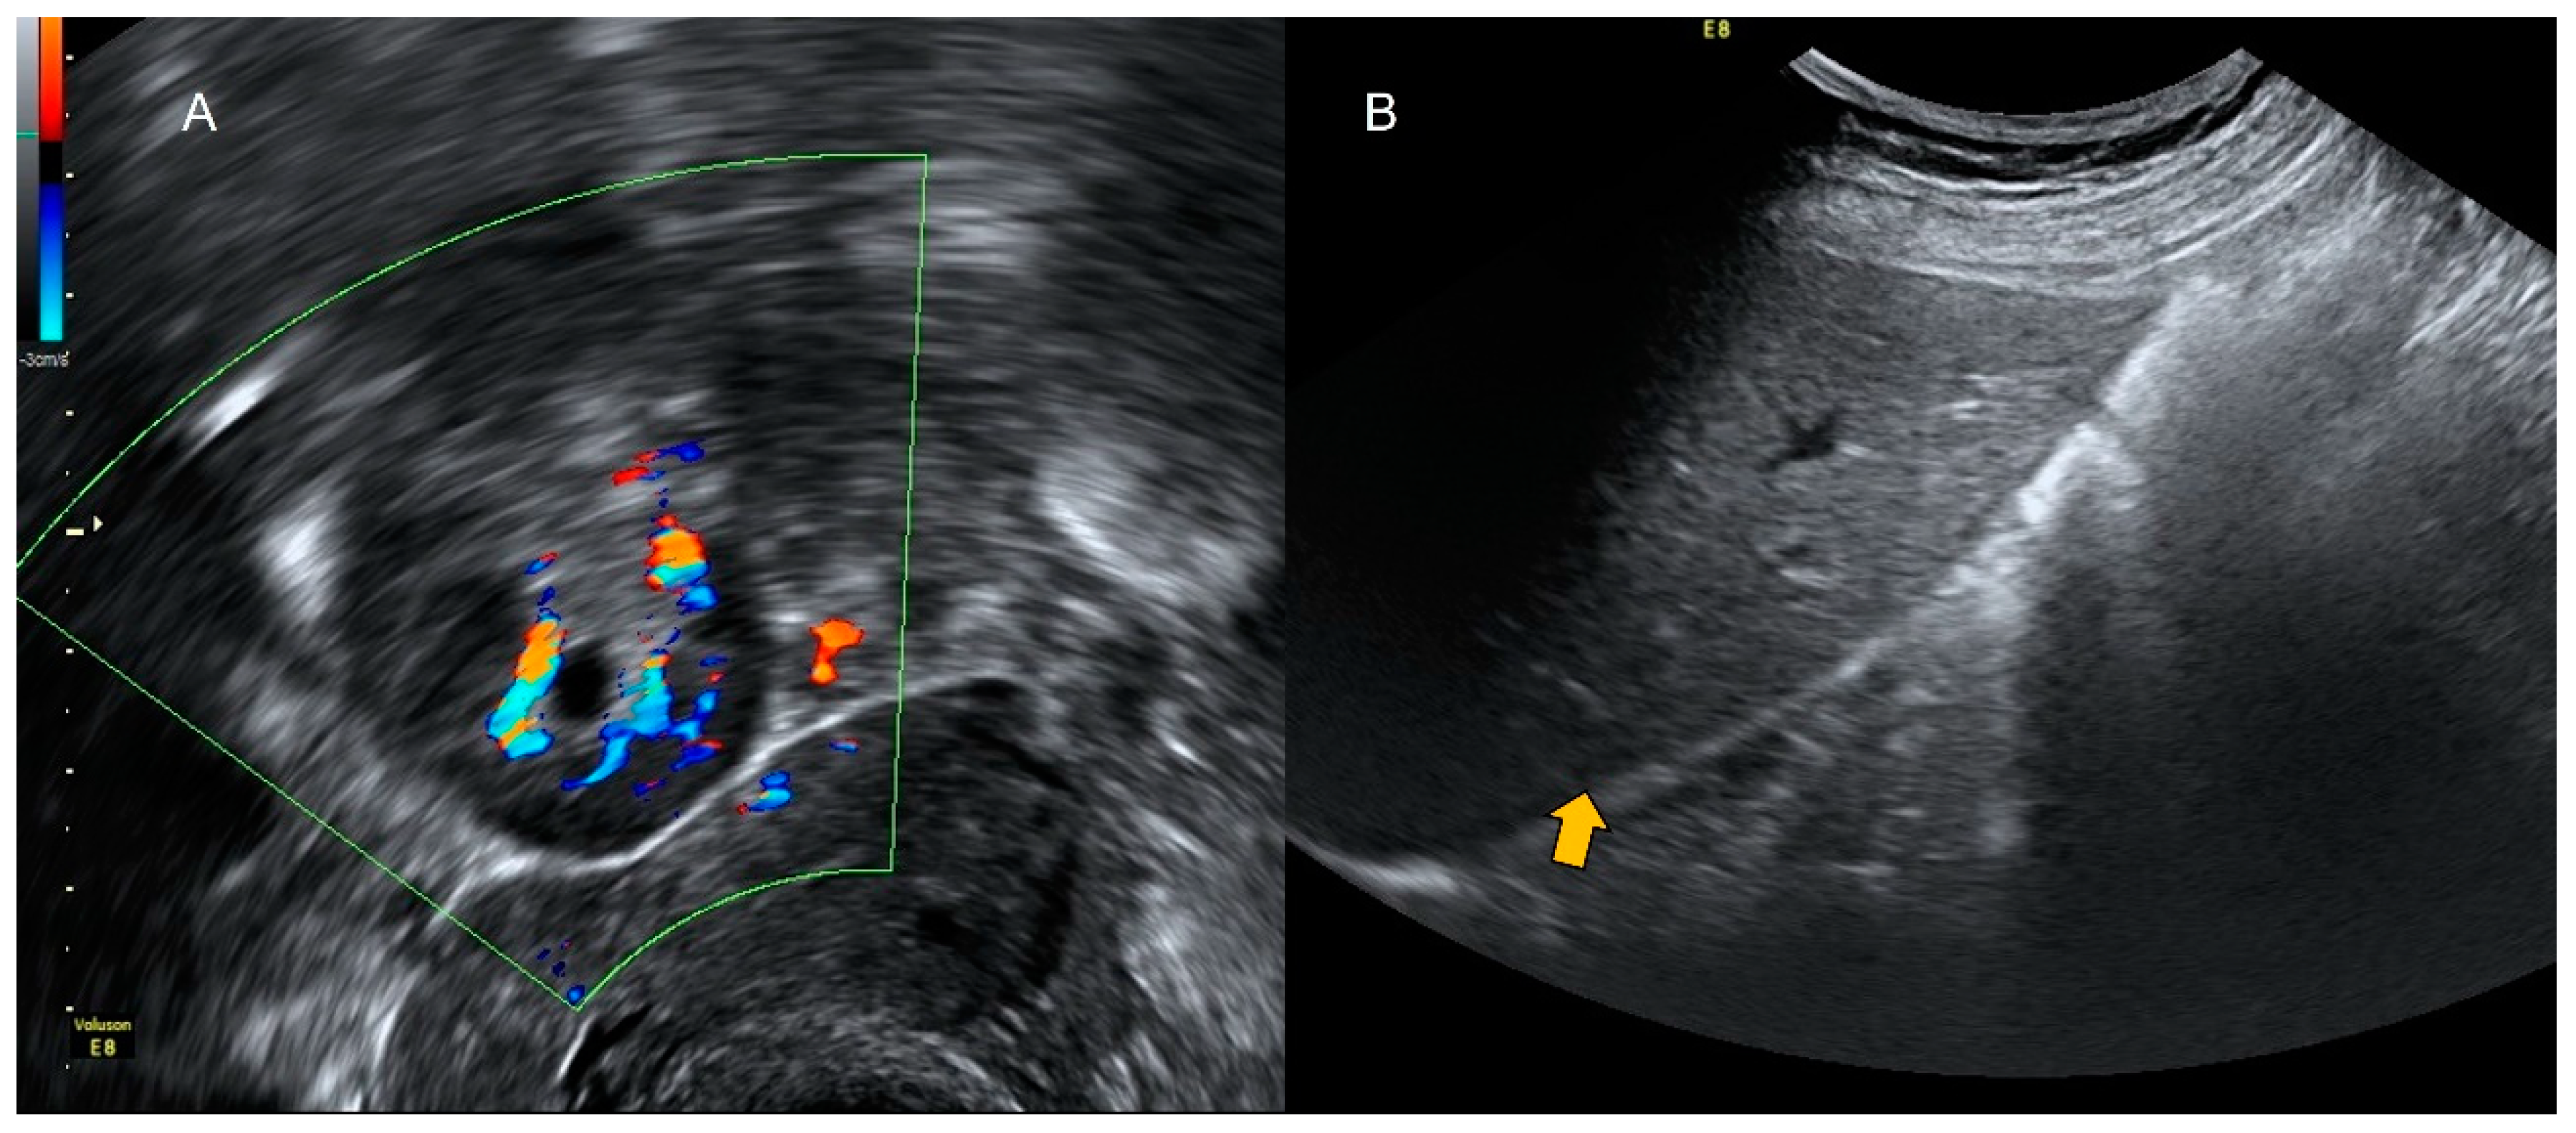

4.1. Pelvic Congestion

4.2. Thrombosis

- Graupera, B.; Pascual, M.A.; Garcia, P.; Di Paola, R.; Ubeda, B.; Tresserra, F. Atypical ultrasonographic presentation of ovarian vein thrombosis. Eur. J. Gynaecol. Oncol. 2011, 32, 439–440. [Google Scholar]